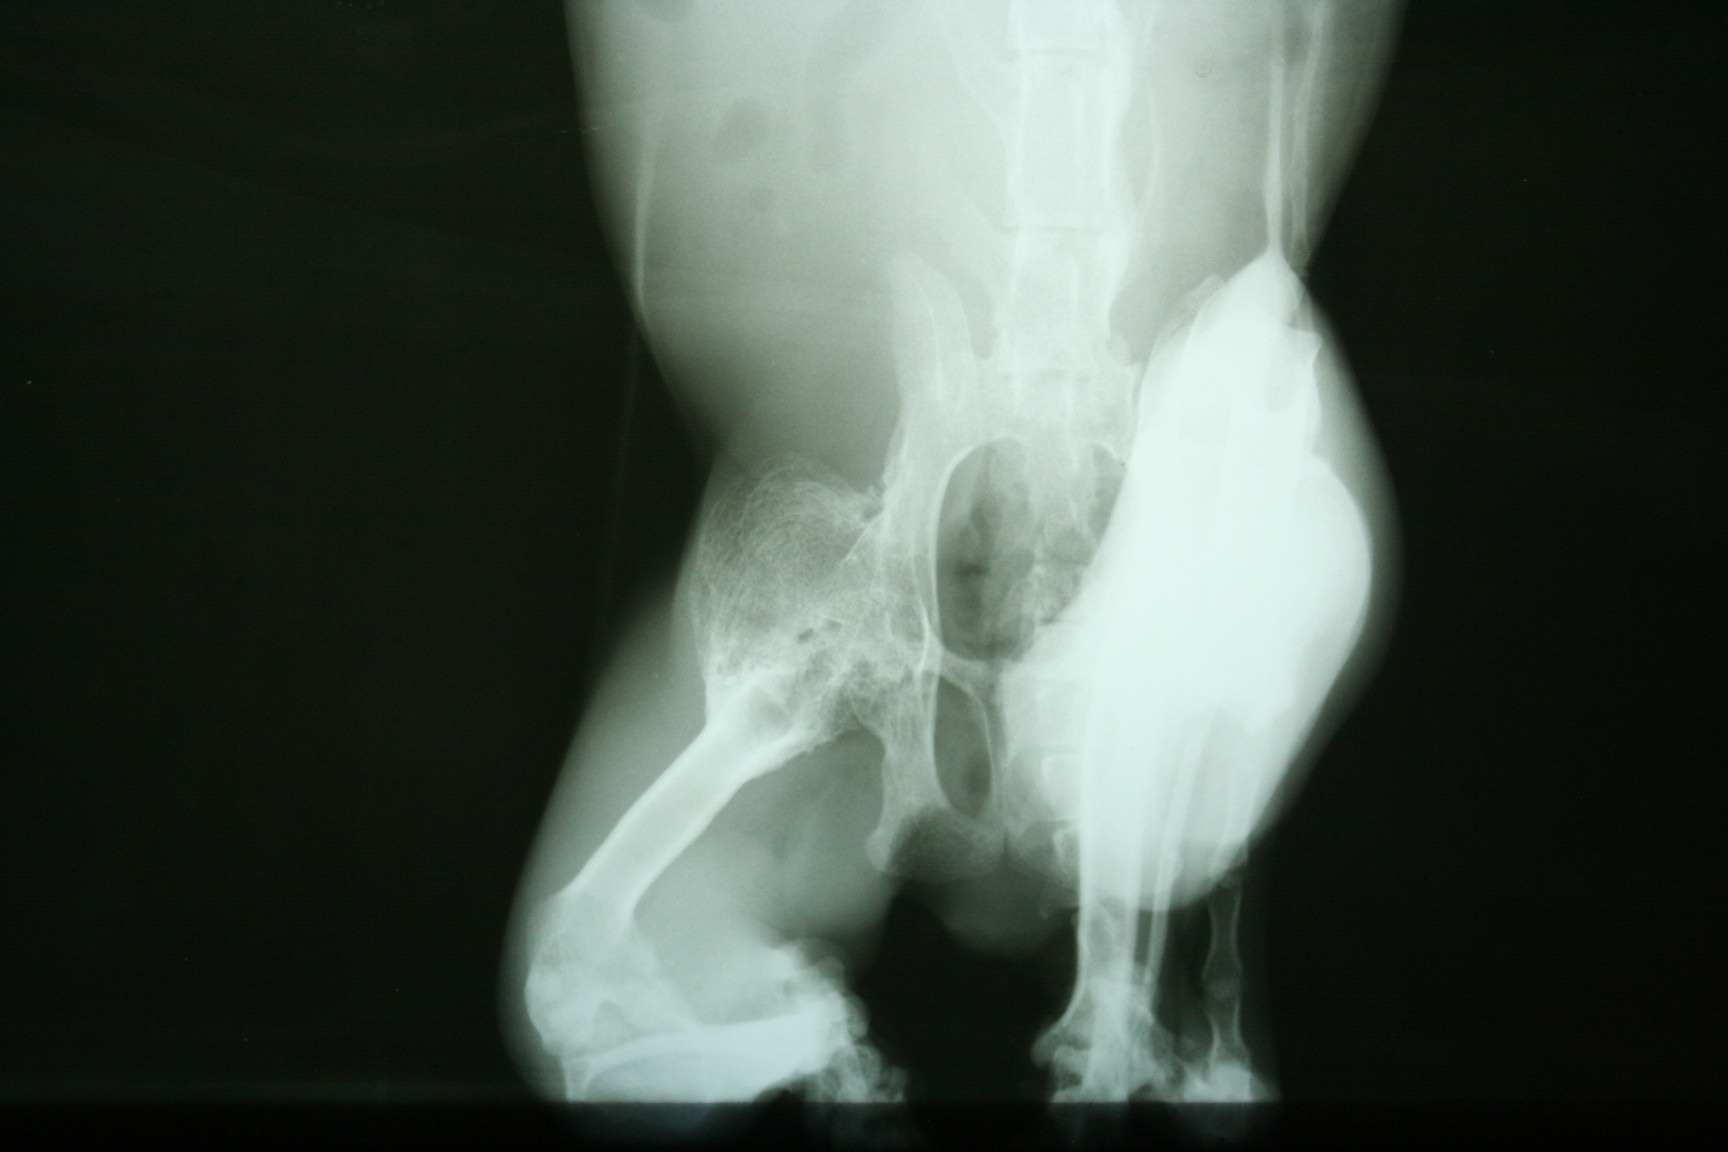

主題: .疑是車禍受傷沒有醫療倒至渾身僵硬.不能行動的貓咪 申請者姓名: 李惠卿 花色: 申請日期: 2013-04-12 17:20:11 申請者部落格: 申請者臉書網址: 所在縣市/合作醫院: 高雄市/回生動物醫院 治療費用: 6200元 需求人數: 7人 已結案 (2013-06-27 14:31:08) 報名人員: 家有三色喵(已付款)、詩詩(已付款)、Pei Shan Lee(已付款)、啾墨韶(已付款)、chiawei x2(已付款)、戀糖bear(已付款)、 候補人員: 動物病情說明: 學生坡網求救的貓咪.一到現場發現貓咪情況非常糟.骨瘦如材.直接就用抱的帶到醫院.貓咪骨頭懷疑是曾經車禍或外力受傷.沒有治療.骨頭不正常的增生.導致渾身僵硬.連頭都無法轉動..貓咪送醫時只能採取保守支持性的治療.灌食營養品..住院十天 後由通報的學生們接回照顧..醫療費用需要大家的幫忙.4000(4/2-4/11 400*10 住院費)+4/2洗澡剪毛600+4/2.4/3 X光片 (400*4)1600=6200